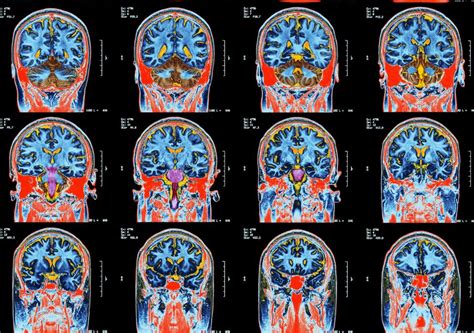

Abnormal Brain Scans In Children With Covid 19 Revealed In Data From 96 Studies